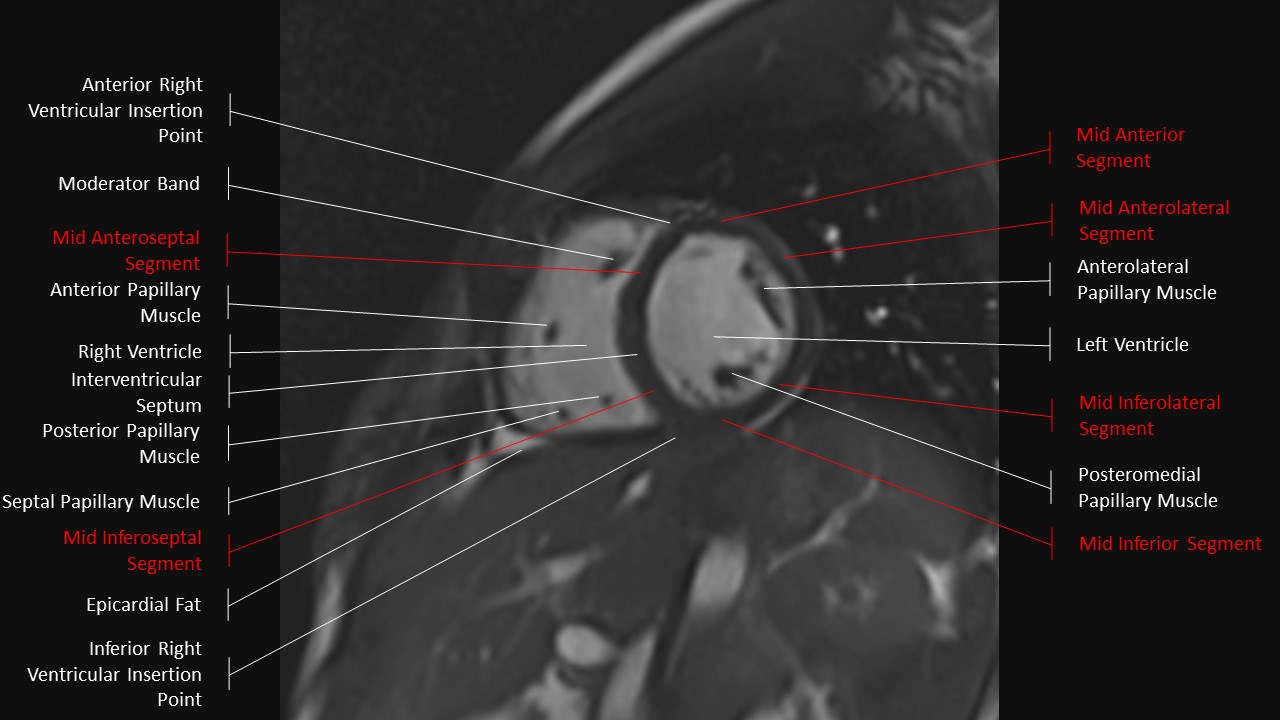

Short Axis Series